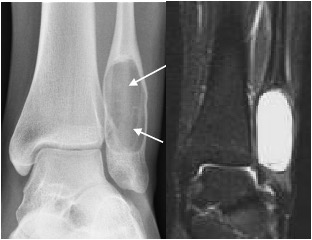

Enchondroma

- Benign cartilaginous tumour

- Typically found in the diaphyses of the metatarsals and phalanges

- Well defined, radiolucent and mildly expansile with cortical thinning

- May have internal calcification

- Multiple enchondromas (as seen in Ollier’s disease) may have malignant potential

Multiple enchondromas (arrows) in Ollier’s disease